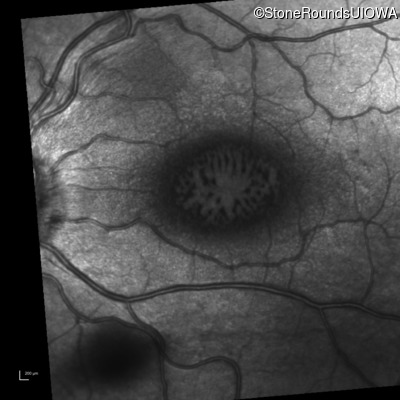

Infrared Fundus Photograph - Right - 20/80 sc

Exemplar